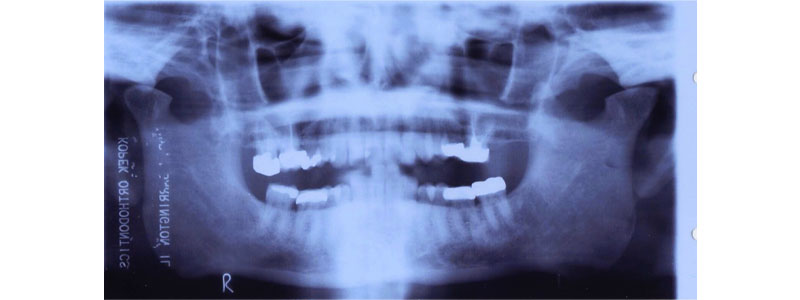

Intra-articular disease or dysfunction must first be evaluated and stabilized before initiating changes to the vertical dimension. A complete TMJ examination is intended to reveal joint pathologies such as disc displacement, crepitus, mandibular mobility, and the joint’s ability to be loaded under function. Additionally, radiographic analysis (such as panoramic X-ray, CBCT, or MRI, as necessary) is utilized to elucidate correct joint anatomy and condylar positions.

Evidence of osteoarthritic change or condylar surface abnormality precludes a change in vertical dimension until stabilization occurs. Additionally, patients who could have difficulty adapting to neuromuscular changes that occur with a change in OVD (e.g., Parkinson’s or elderly patients) should be avoided. Occlusal splint therapy is utilized to help stabilize and evaluate joint position before comprehensive restorative measures.